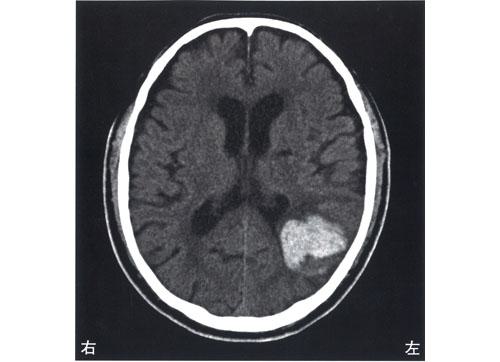

脳梗塞の発生部位によって出現する症状は異なります。この問題では、それぞれの部位における症状を正確に理解することが求められています。

右小脳半球では、右(同側)上下肢の運動失調が見られるため、この選択肢は誤りです。小脳半球の症状には、同側上下肢の運動失調や筋緊張の低下が含まれます。

右内包後脚では、左上下肢の運動麻痺が見られるため、この選択肢は正しいです。